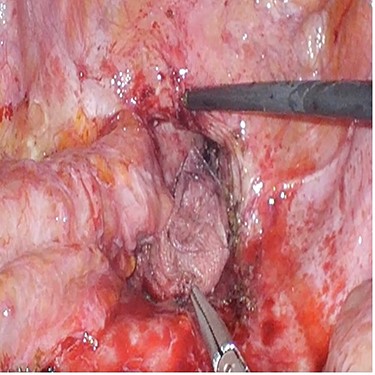

A 72-year-old man underwent open low anterior resection with covering ileostomy for mid rectal cancer at another hospital after completion of long-course neoadjuvant chemoradiotherapy. Ileostomy reversal was performed 3 months after surgery. He developed intestinal obstruction secondary to anastomotic recurrence 6 months later. Sigmoidoscopy and biopsy confirmed the presence of recurrent adenocarcinoma. CT abdomen showed infiltrating soft tissue mass at right pelvic cavity with involvement of presacral area and ileal loop. He was admitted to our centre and underwent laparoscopic small bowel resection. Intraoperatively, small bowel was adherent to pelvic cavity and site of recurrence resulting in proximal small bowel dilatation (Fig. 2). Small bowel adherent to the recurrence site was resected and side-to-side small bowel anastomosis was performed. The anastomotic recurrence was unresectable (Fig. 3). Transabdominal pelvic drain was inserted followed by mesh placement. He was discharged after 8 days and after a follow-up of 12.1 months, did not develop further small bowel obstruction.

Case 3—unresectable anastomotic recurrence after resection of adherent small bowel.